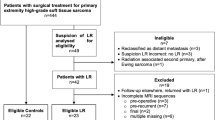

From June 2016 to January 2022, we retrospectively evaluated 64 consecutive patients with extremity STS who underwent post-surgical MRI for scheduled follow-up (n = 52) or because of Whoops surgery or with positive margins after planned excision (n = 12).

Study population included 64 patients, 35 males and 29 females, with age range 10–94 and mean age 52.36 years. Pre-operative histological diagnoses and anatomic sites of tumors are reported in Table 2.

Based on the diagnostic criteria mentioned in Materials and Methods section, a total of 38 lesions in 30/64 patients were diagnosed on MRI as local recurrence or residual disease of STSs (2 patients with 2 nodules and 3 patients with 3 nodules). One out of these 30 patients was diagnosed as positive on MRI (ADC 0.8 × 10–9 m2/s), but no recurrence or residual disease in the post-surgical specimen was observed, resulting in a false positive. The other 37/38 lesions in 29 patients were confirmed by post-surgery histopathological evaluation. Among these 29 patients, 9 cases were positive after Whoops or positive margin at surgery (solitary lesions), while in 20 cases a total of 28 lesions were diagnosed as local recurrence; the histologic diagnoses are reported in Table 3. Out of 37 histologically proven nodules, 16 lesions (43%) had the maximum diameter equal or smaller than 1 cm and 21 greater (57%). Particularly, the mean and the range of the recurrence’s maximum diameter were 24 mm and 3–100 mm, respectively.

Excluding Whoops cases, the mean, the mode, and the range of time between surgical tumoral excision and first diagnosis of STSs recurrence are 18.5, 5, and 2–66 months, respectively.